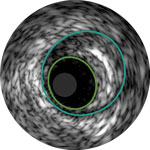

Behandlungsplan Beispiel 1

Lumen

Exzentrische fibröse Plaque mit tiefliegendem Calcium

Schallschatten

Gefäßgröße: 5,5 mm Durchmesser Plaquemorphologie: fibröse Plaque mit intimalem und mittlerem Calcium Plaquegeometrie: exzentrische Läsion Position des Führungsdrahtes: wahres Lumen

Quick-Cross-Katheter: souverän komplexe Morphologien durchqueren Direktionale Atherektomie mit Phoenix: frontal zum Schneiden, Erfassen und Freilegen gemischter Morphologien, einschließlich Kalzium; Möglichkeit der Richtungssteuerung für größeren Lumengewinn AngioSculpt Scoring-Ballonkatheter: Calcium messen, um eine Dissektion zu reduzieren4 Stellarex DCB: entwickelt für hohe Leistungsfähigkeit bei Kalzifizierungen